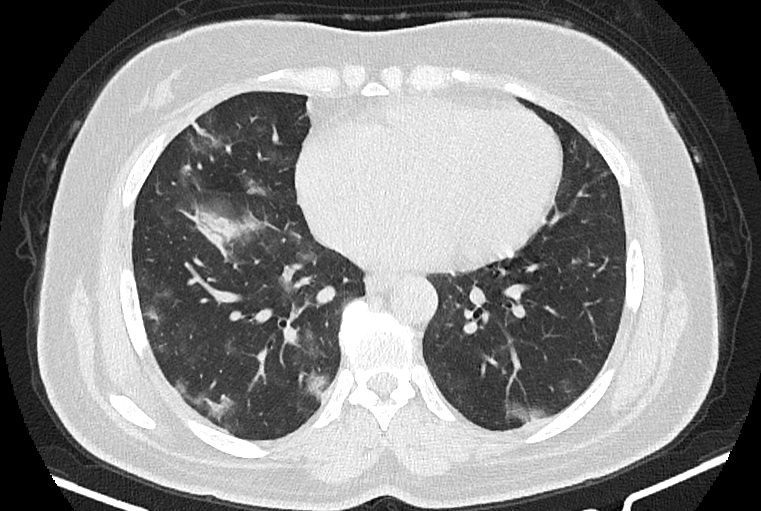

در HRCT از ريه ها(اسپيرال ، مولتي ديتکتور 16، مقاطع اگزيال با ضخامت 1mm بدون فاصله ) ، بدون كنتراست تزريقي :

-Ground glass opacities Patchy پراکنده در ريه ها مشهود است که مطرح کننده Viral pneumonia مي باشد . ( با درگيري 20 درصد حجم ريه )

نتیجه : Highly suggestive of COVID-19